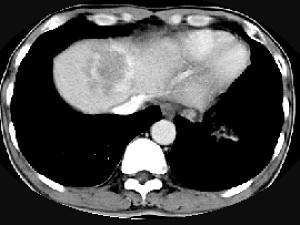

问题 男,61岁,寒战高热,右上腹痛,白细胞计数升高,CT检查如图,最可能的诊断是 ( )

选项 A、炎性肉芽肿 B、肝转移瘤 C、肝血管瘤 D、肝脓肿 E、原发性肝癌

答案 D